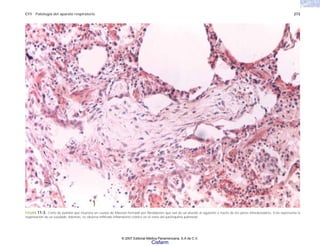

FIGURA 2-5. Histología de la piel en la esclerodermia, con abundante colágena por debajo del nivel de

las glándulas sudoríparas.